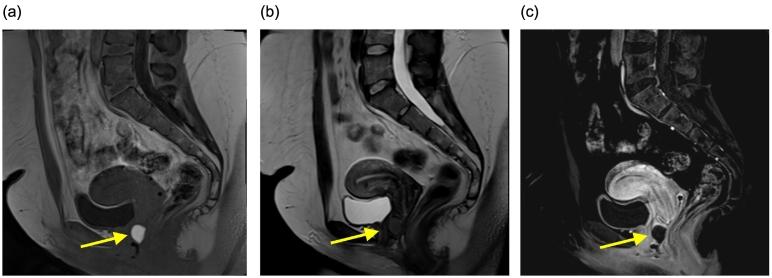

A 23-year-old patient with an asymptomatic anterior vaginal wall cyst was referred to gynecology for evaluation and treatment. Preoperative assessment with physical examination and magnetic resonance (MR) imaging of the pelvis was most consistent with Gartner's cyst. Following resection of the cyst wall, histologic evaluation demonstrated endometrial glands, hemosiderin-laden macrophages and inflammation, consistent with vaginal wall endometrioma. This case highlights challenges in the diagnosis of endometriosis in the vagina and in other rare locations, possible mechanisms of development, and proposed treatments.

一名23岁无症状阴道前壁囊肿患者被转诊至妇科进行评估和治疗。术前通过体格检查和盆腔磁共振成像评估,最符合加特纳囊肿。囊肿壁切除术后,组织学评估显示有子宫内膜腺体、含铁血黄素巨噬细胞和炎症,符合阴道壁子宫内膜异位症。该病例突出了阴道及其他罕见部位子宫内膜异位症诊断中的挑战、可能的发病机制及建议的治疗方法。